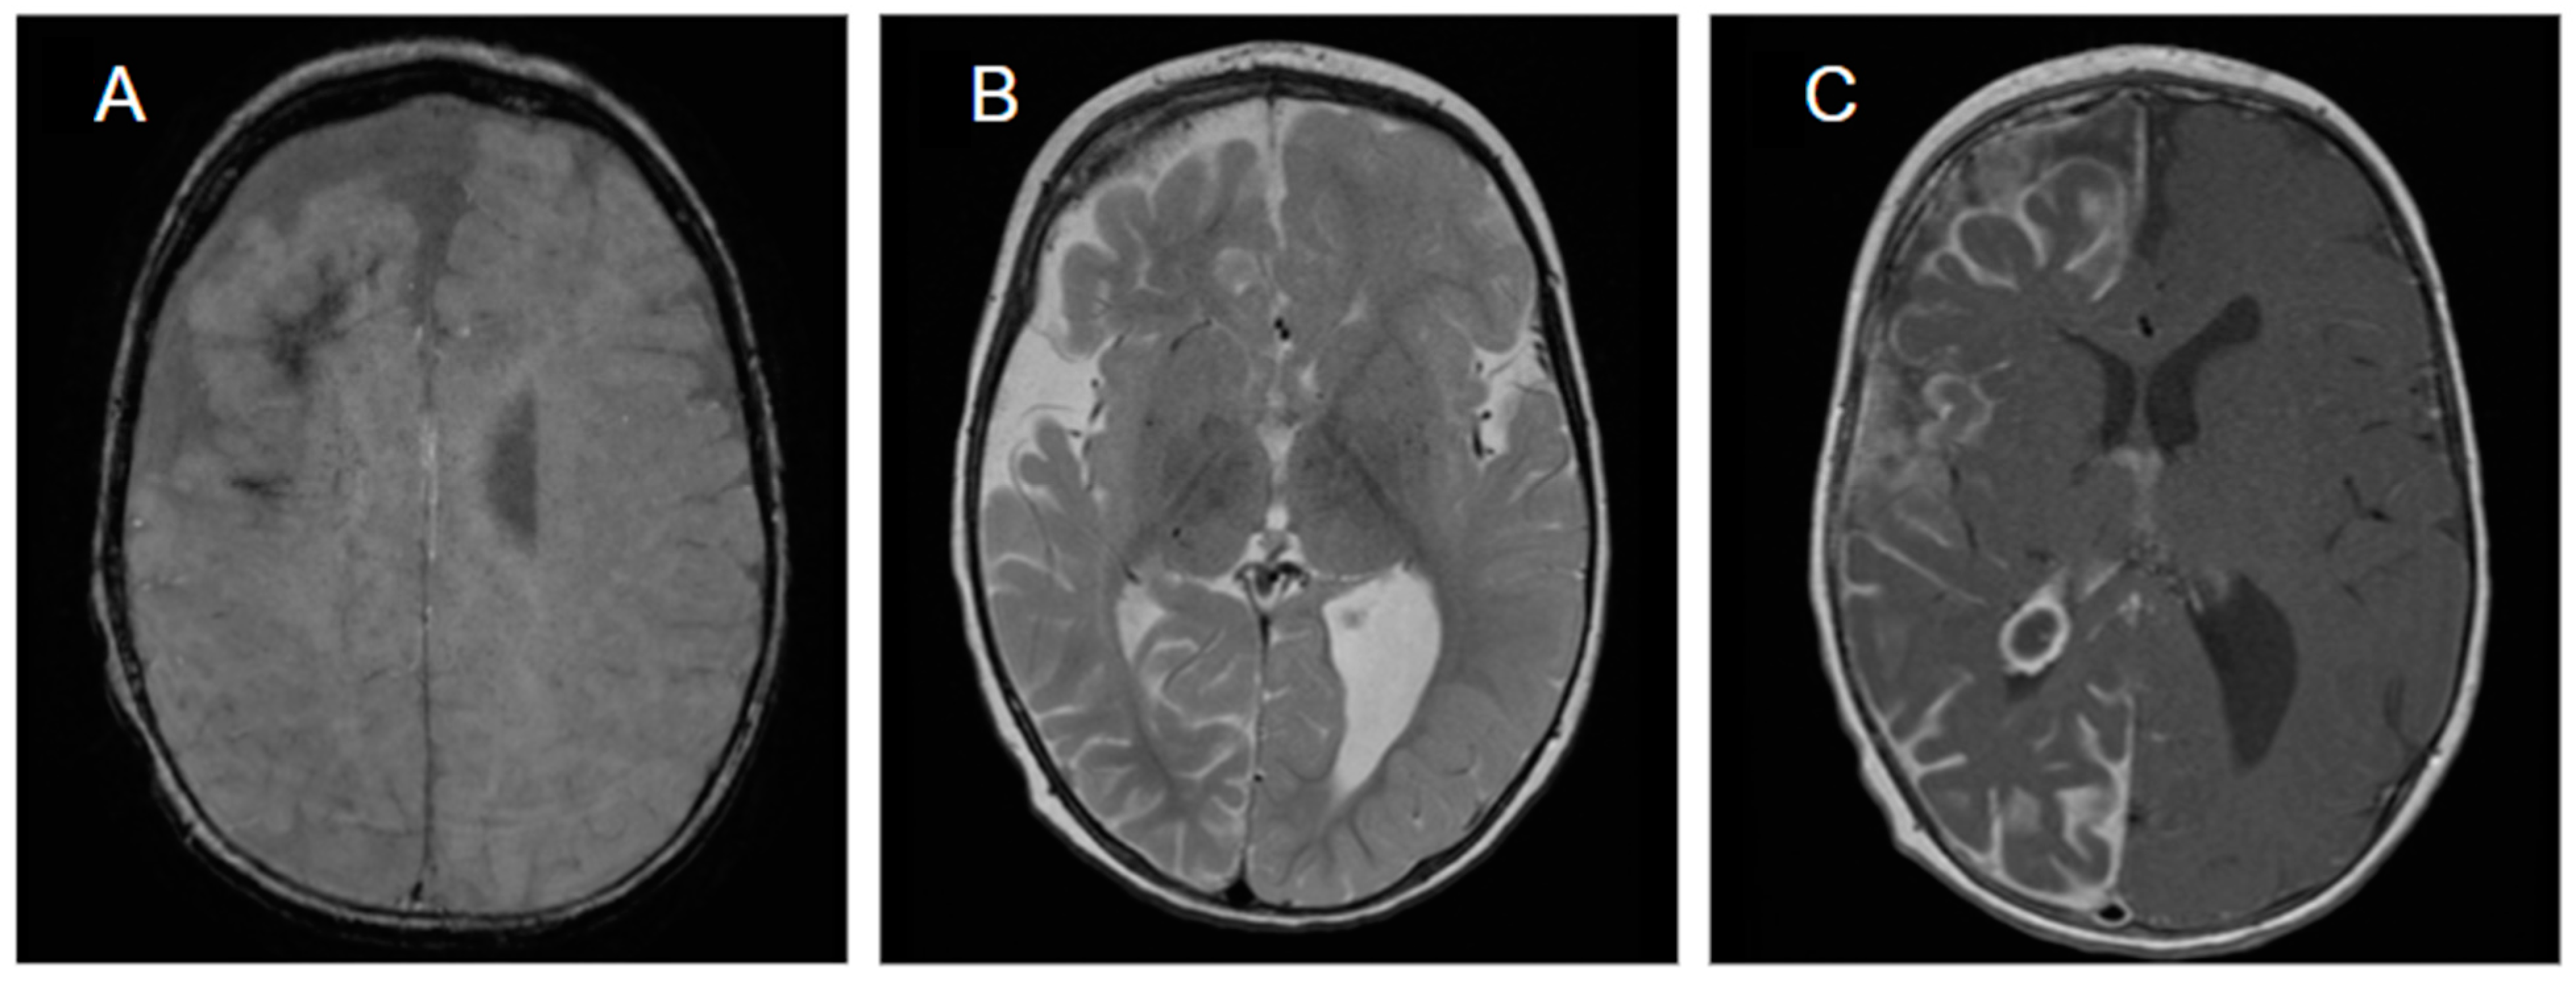

5.1. Diagnosis